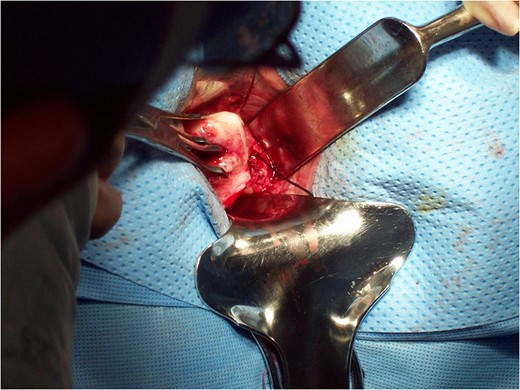

Vaginal examination was then done to place the speculum into the vagina and put a single tooth tenaculum on the anterior lip of her cervix and an Acorn uterine manipulator at the cervix to use for manipulation of the uterus during the laparoscopic portion. Repositioning the patient for the laparoscopic approach through the SPA, the infundibulopelvic ligament, round ligament, fallopian tubes and ovaries were first divided. The broad ligaments were dissected down to the level of the uterine arteries to mobilize the structures. Hysterectomy and bilateral salpingo-oophorectomy were then completed vaginally (Figs

6 and

7). The vaginal cuff was closed by baseball stitches first then with running interlocking stitch of chromic. The cuff was closed from the superior angle to inferior angle and the uterosacral ligaments were approximated to help with vaginal vault support.

Figure 7:

Completion of vaginal hysterectomy.